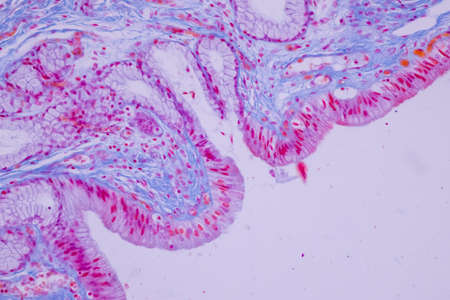

Abstract science background- pyloric division of the stomach of the dog. Cell biology